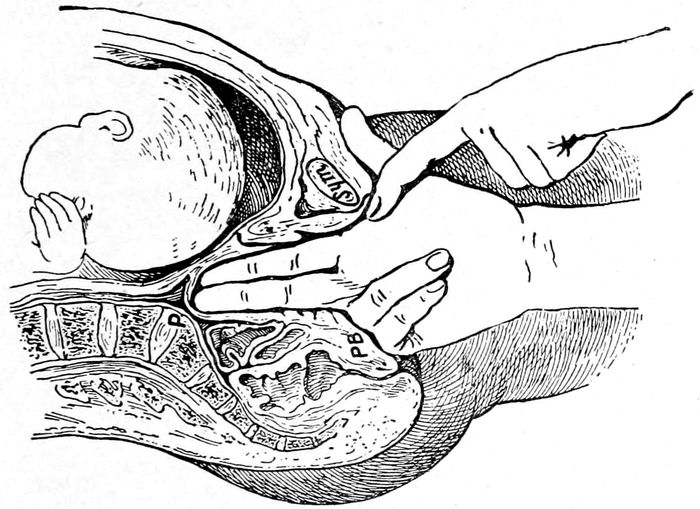

| 98. |

Measuring the diagonal conjugate with the finger |

219 |

| |